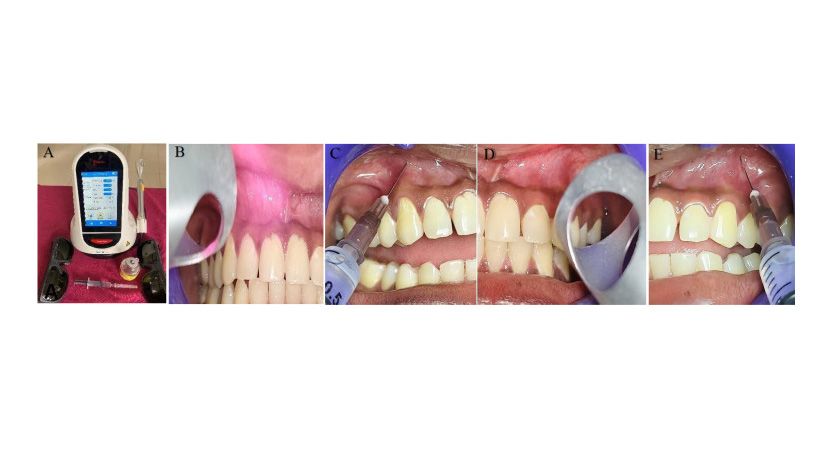

Odontología General

Dispositivos dentales y resistencia antimicrobiana

Desafíos, innovaciones y cumplimiento normativo